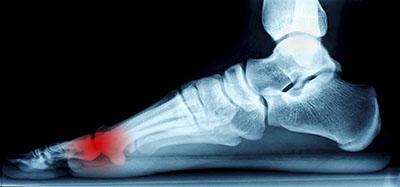

Ankle pain, while initially thought of as an issue for athletes, can affect anyone at anytime. Simple, everyday activities, such as walking or running on an uneven surface, have the possibility of causing serious harm to one’s ankle. That is, however, not to discount...